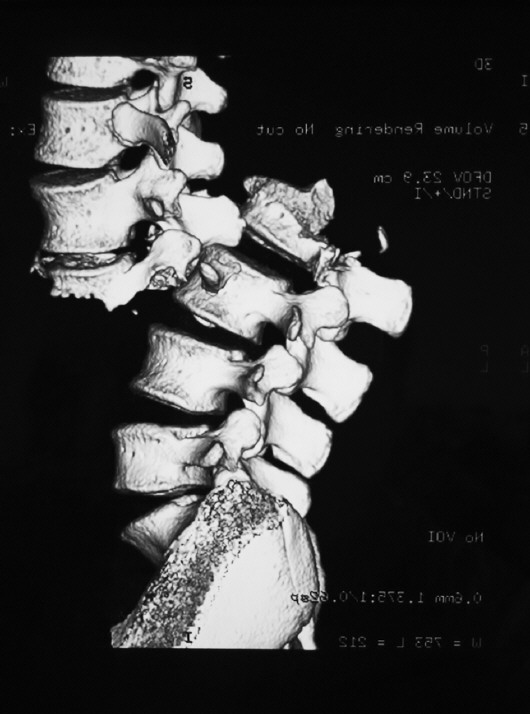

该患者的腰椎脱位影像图。

滨医附院脊柱外科主任耿晓鹏介绍,这名患者入院时血压不稳定,“高压只有80,低压才40,腰背部严重后凸畸形,腰背部皮下大量积血,而且大小便失禁,还伴有血尿。”医生紧急为患者进行了详细检查,影像学检查显示,这名患者L2椎体骨折脱位,脱位程度严重“全脱位是4度,但是这名患者脊柱脱开位置如果量的话有两个半椎体的位置,他还有侧方位的移位,非常严重,我们说他这个脱位有‘10度’,患者的椎管神经结构已经断了,下肢没有任何功能了。”经过科室医生讨论后,为这名18岁的患者在全麻下行腰椎骨折脱位闭合手法复位术。